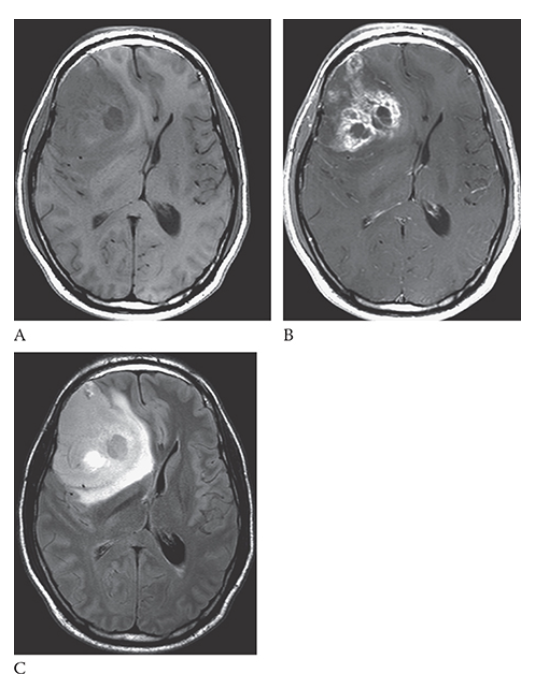

What is A

Ischemic Stroke. Axial T1W image shows an area of low signal in the white matter and increased signal of the gray matter in the right posterior parietal lobe. An axial T2W image

What is B

Ischemic Stroke. Axial T1W image shows increased signal in this area consistent with edema. FLAIR

What is C

Ischemic Stroke. Axial T1W image shows increased signal in the white and gray matter in this region.